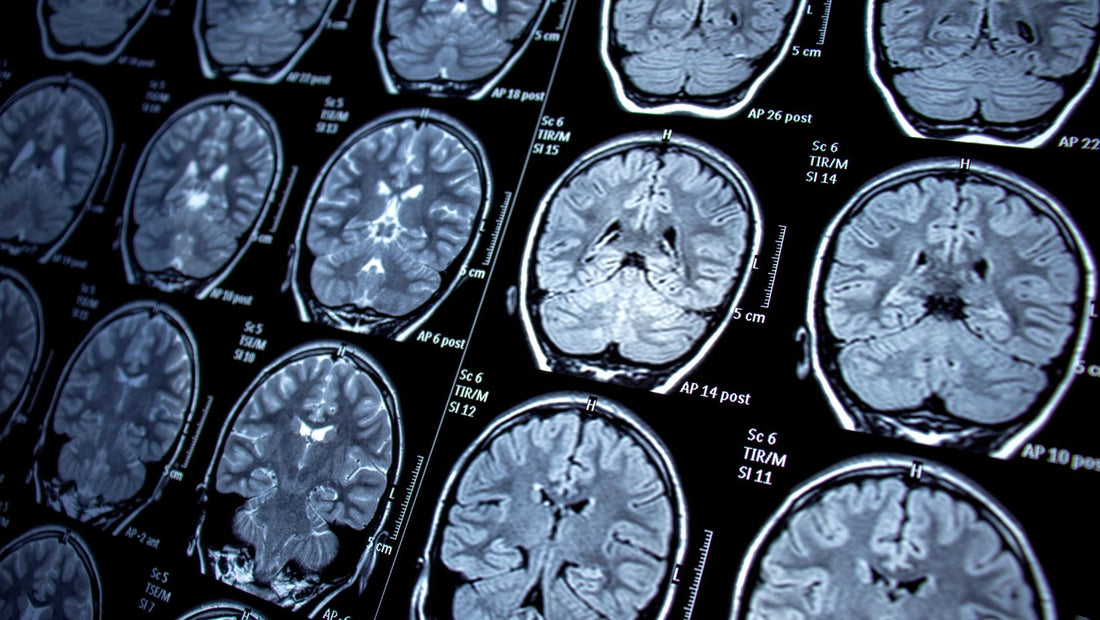

🧠 The Neuroscience of Journaling

Research shows that expressive writing activates the prefrontal cortex, the brain region responsible for emotional regulation and decision-making. Studies published in Psychological Science demonstrate that just 15-20 minutes of journaling can reduce cortisol levels by up to 23%.

Research from UCLA shows that mindful writing practices increase gray matter density in areas associated with learning, memory, and emotional regulation. This is the biological foundation of 'the glow' you'll experience.